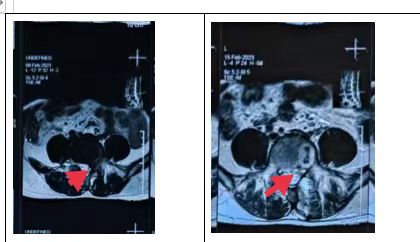

术前术后MRI对比

来就诊的患者大都是长期饱受腰腿痛的折磨,已经严重影响了正常的行走坐立,生活质量严重下降,多方求医尝试了很多治疗方法仍未得到明显好转和根除。我院脊柱外科团队仔细研究每位患者病情,针对每位患者制订个性化治疗方案,选择利用国内较为前沿的新型脊柱微创技术——微创双通道内镜技术(UBE技术)为病人解决难题。脊柱外科团队在完善术前必要检查的前提下,制订了详尽完备的术前规划,分别为患者实施了UBE下椎管扩大减压手术,改术式仅通过2个1cm的小切口便完成了神经减压操作,出血量不到50ml,术后患者腰腿痛症状明显消除,恢复理想,患者及家属对手术疗效非常满意。